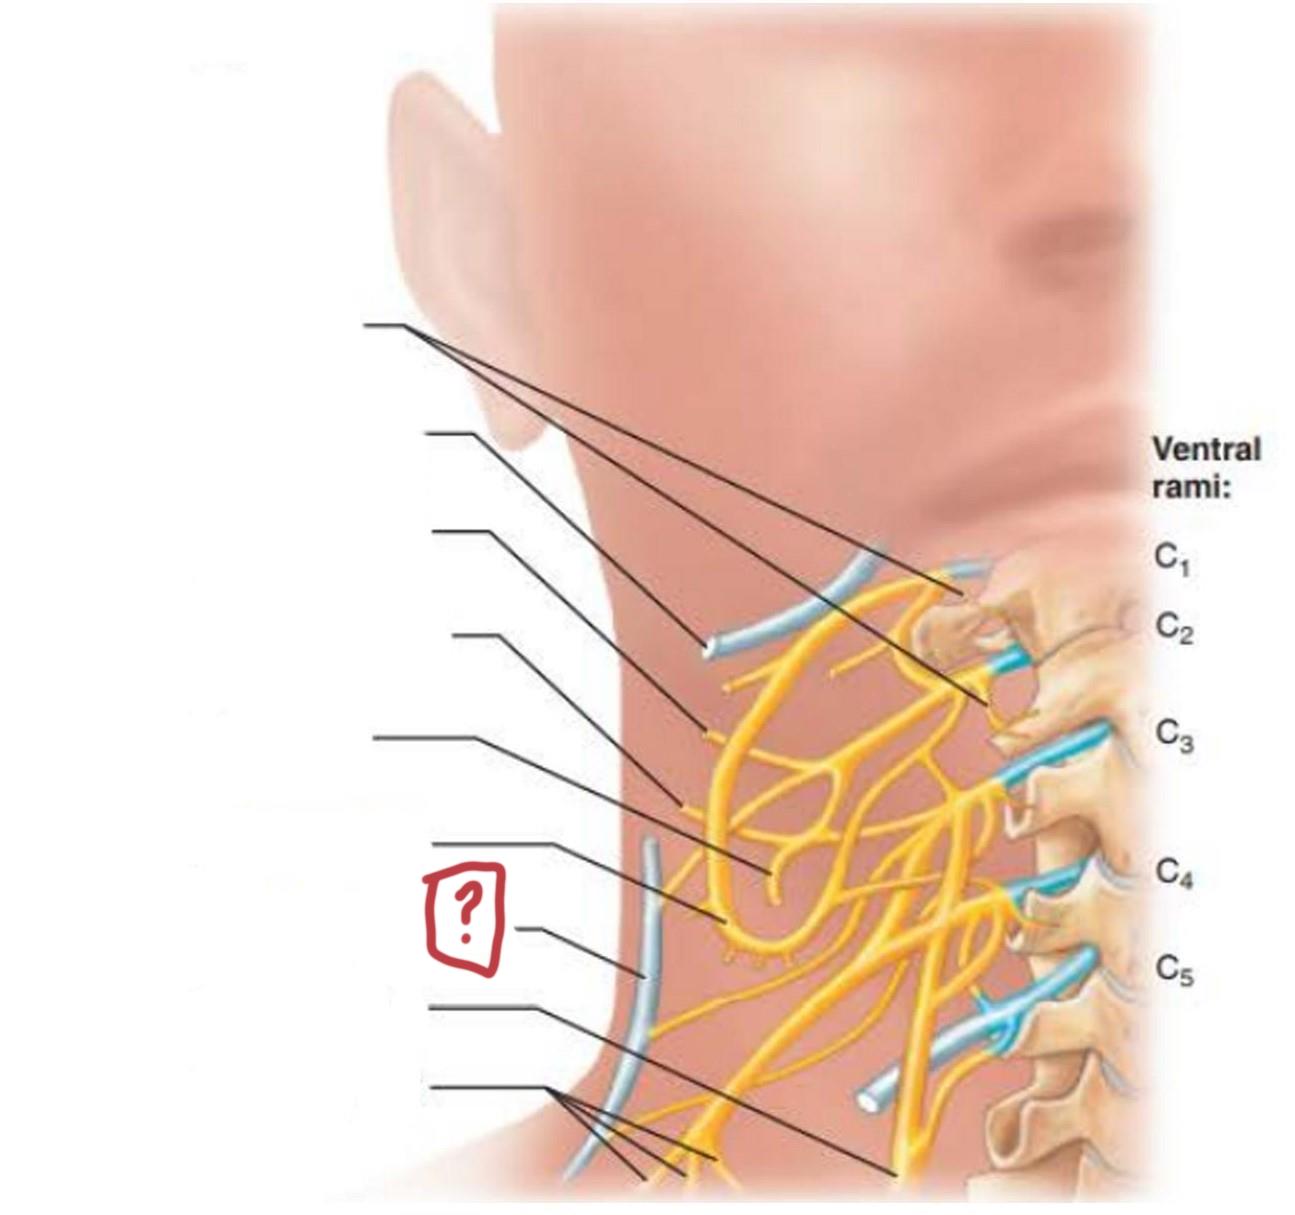

cervical plexus

C1-C4

segmental branches

hypoglossal nerve (12)

lesser occipital nerve

greater auricular nerve

transverse cervical nerve

ansa cervicalis

accessory nerve (11)

phrenic nerve

supraclavicular nerves